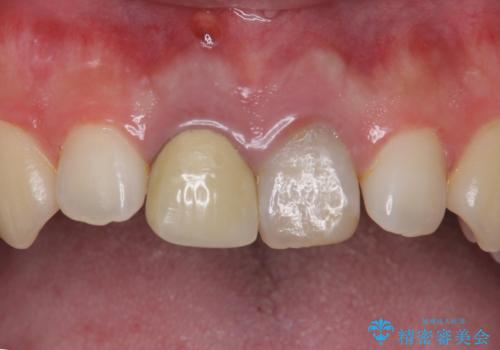

二本とも神経の治療のやり直し(再治療)を行ってからセラミックを入れています。

今回は、前歯のかみ合わせが深く、下の前歯が根元にかみこむような状態だったため、オールセラミックは難しく、メタルボンドクラウン(金属の裏打ちにセラミックが盛ってあるクラウン)となりました。